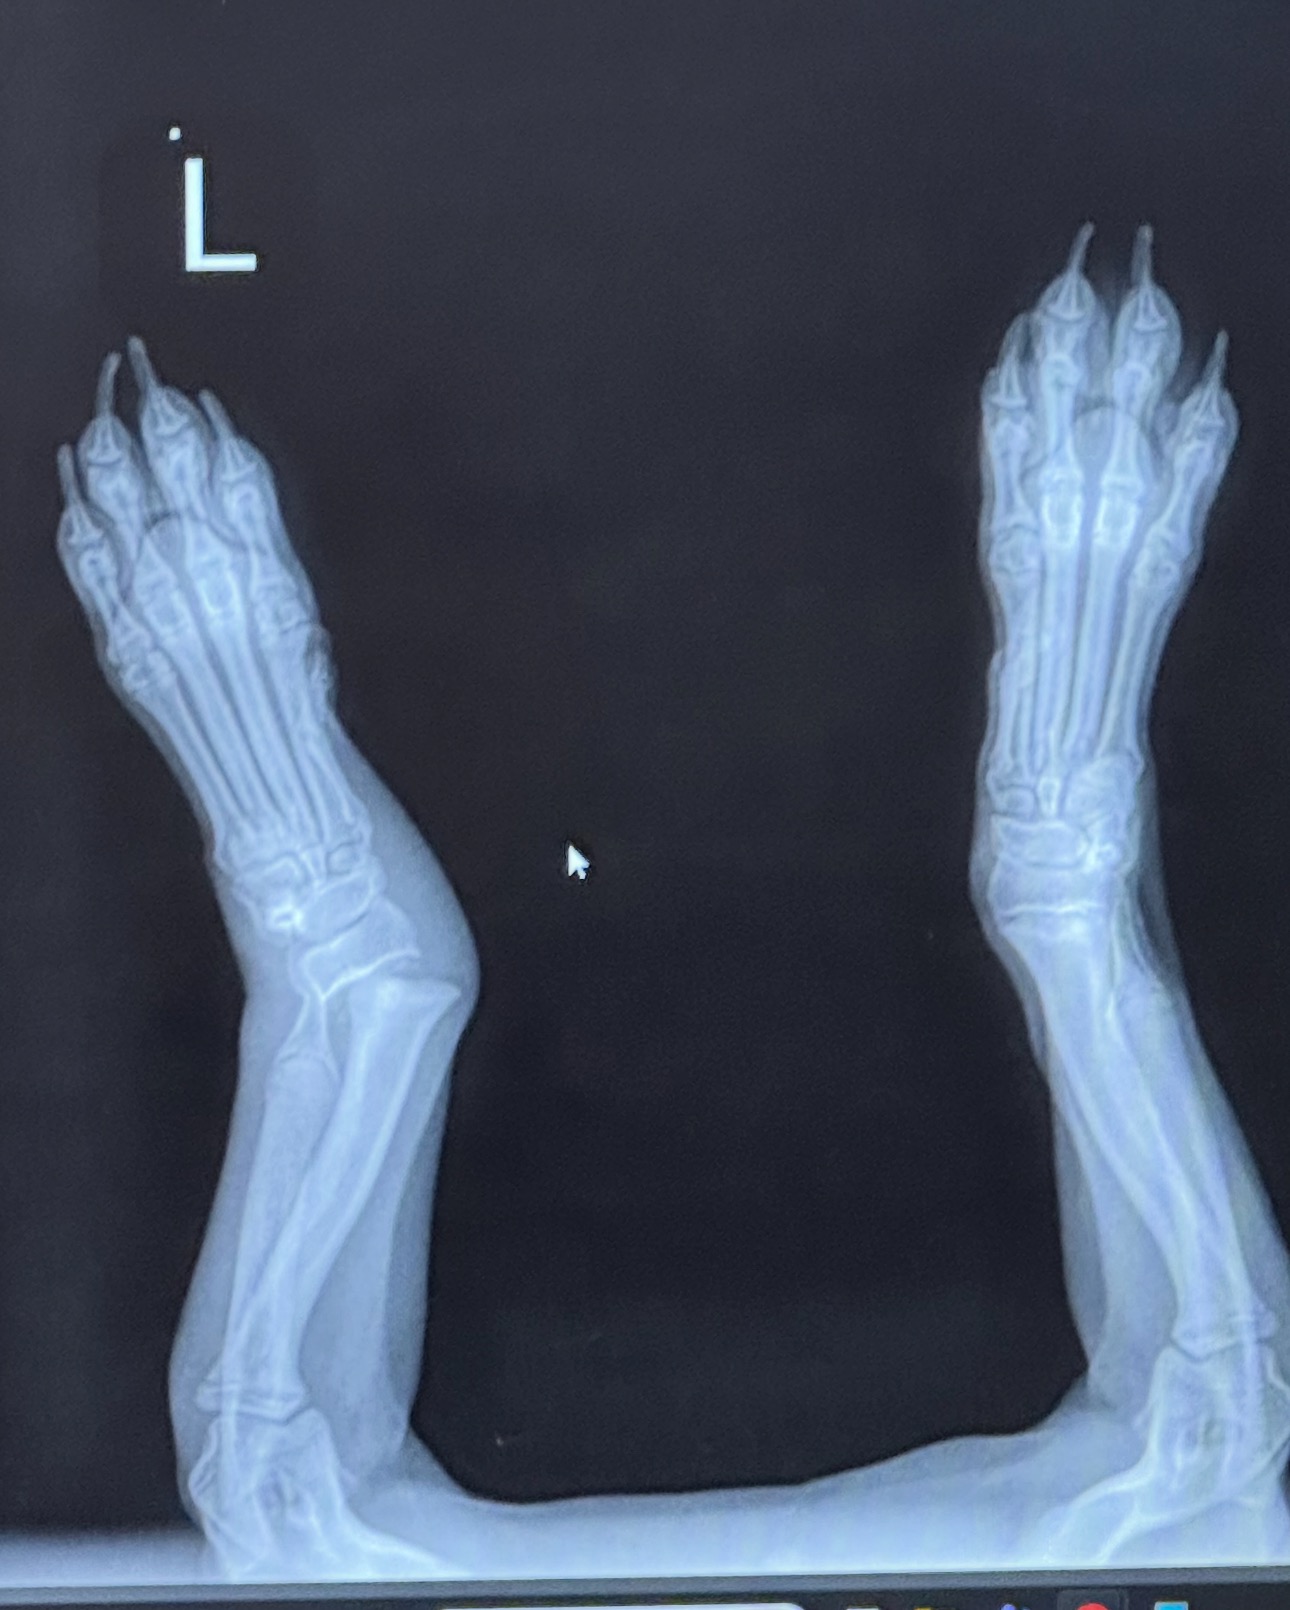

My 4-month-old puppy Leia was accidentally injured and broke her front left leg. She now urgently needs growth plate surgery, which is something I truly cannot afford on my own. Right now, she’s in a cast that needs to be changed every 3–4 days, and the expenses are adding up so fast. I’m trying everything I can to help her. If Leia doesn’t get this surgery, she could live the rest of her life in severe pain, develop limb deformities, or even lose her leg. I don’t want that future for her.